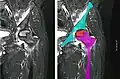

X-ray images of avascular necrosis in the early stages usually appear normal. In later stages it appears relatively more radio-opaque due to the nearby living bone becoming resorbed secondary to reactive hyperemia.[2] The necrotic bone itself does not show increased radiographic opacity, as dead bone cannot undergo bone resorption which is carried out by living osteoclasts.[2] Late radiographic signs also include a radiolucency area following the collapse of subchondral bone (crescent sign) and ringed regions of radiodensity resulting from saponification and calcification of marrow fat following medullary infarcts.

Nuclear magnetic resonance of avascular necrosis of left femoral head. Man of 45 years with AIDS. -